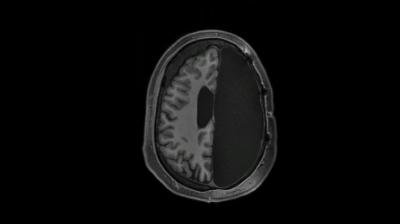

video: A view of a structural magnetic resonance image (MRI, axial orientation) showing slices from the top to the bottom of the brain of an adult who had one complete hemisphere resected in childhood due to epilepsy. Global interhemispheric connectivity remains intact, yet with increased connectivity between networks, supporting cognition despite atypical brain anatomy.

Image:

Caltech Brain Imaging Center